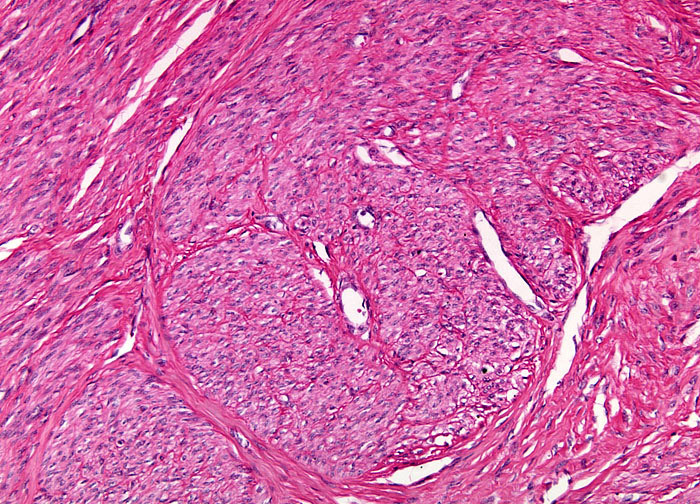

Webpathology.com: A Collection Of Surgical Pathology Images

www.webpathology.com

www.webpathology.com

leiomyoma uterus myxoid webpathology comments pathology

Webpathology.com: A Collection Of Surgical Pathology Images

webpathology.com

webpathology.com

leiomyoma myxoid change pathology webpathology comments

Webpathology.com: A Collection Of Surgical Pathology Images

www.webpathology.com

www.webpathology.com

uterus myxoid leiomyoma muscle smooth webpathology pathology fibrillary cells nuclei comments